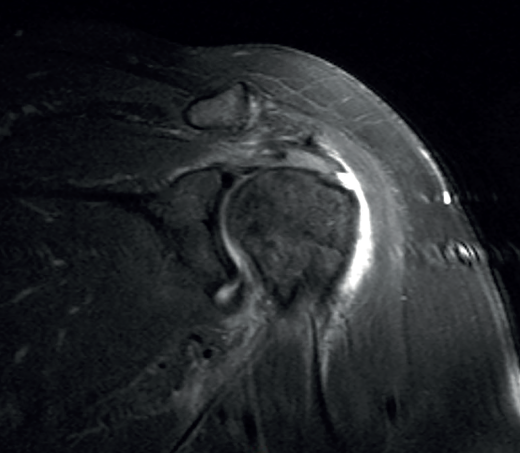

Figure 6. Severe supraspinatus tendinopathy in T2-weighted imaging.

The characteristic MRI image of tendinosis consists of a focal or intra-substance zone of intermediate signal intensity in T1-weighted imaging which does not disappear in T2 sequencing and does not reach fluid signal intensity in T2-weighted imaging (Figure 6). We can sometimes observe diffuse or focal thickening of the tendon, without evidence of rupture(33). Tendinosis may prove difficult to distinguish from early-stage partial rupture of the tendon.

Figure 7. Supraspinatus bursal partial thickness rupture in magnetic resonance imaging scan.

A lesion is classified as being of partial thickness if an abnormal fluid signal intensity in T2 sequencing is seen to extend through a portion of the tendon without affecting its full thickness (Figure 7). These may be bursal or articular lesions, though the latter are more common. There is a possibility that the thickness of the partial lesion may be occupied by scar or granulation tissue, thereby complicating the diagnosis. It has been suggested that the use of arthroMRI in the ABER (abduction + external rotation) position can improve the diagnosis and the typing of these injuries(34). According to Ellman(35), partial thickness lesions can be classified into three grades: grade I (lesion depth < 3 mm), grade II (depth 3-6 mm) and grade III (depth > 6 mm). Taking into account that a healthy supraspinatus measures between 10-12 mm in thickness, grade II lesions affect over 50% of this thickness. Intra-substance lesions are characterized by a fluid-type signal in the thickness of the tendon, without extending to the bursa or joint space.